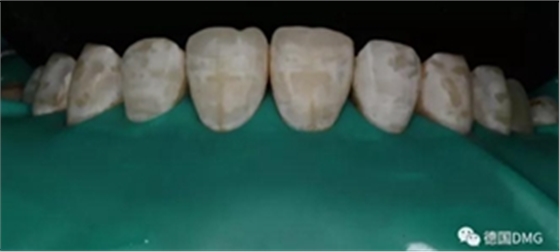

6、去除橡皮章拋光

拋光第一步 用矽粒子去除唇腭側(cè)多余樹脂,平整牙面,后使用高級(jí)樹脂拋光套裝逐步拋光。這一步目的在于高度拋光樹脂和釉質(zhì)復(fù)合牙面。

術(shù)后顯示,滲透樹脂恢復(fù)了天然牙釉質(zhì)的折光率(天然通透牙釉質(zhì)折光率1.62滲透樹脂折光率是1.52)顯的很自然,很有光澤。完全是天然牙質(zhì)的顏色。

(下圖是拋光完成)

治療完成的上頜牙齒和未治療的下頜牙齒形成明顯對(duì)比。